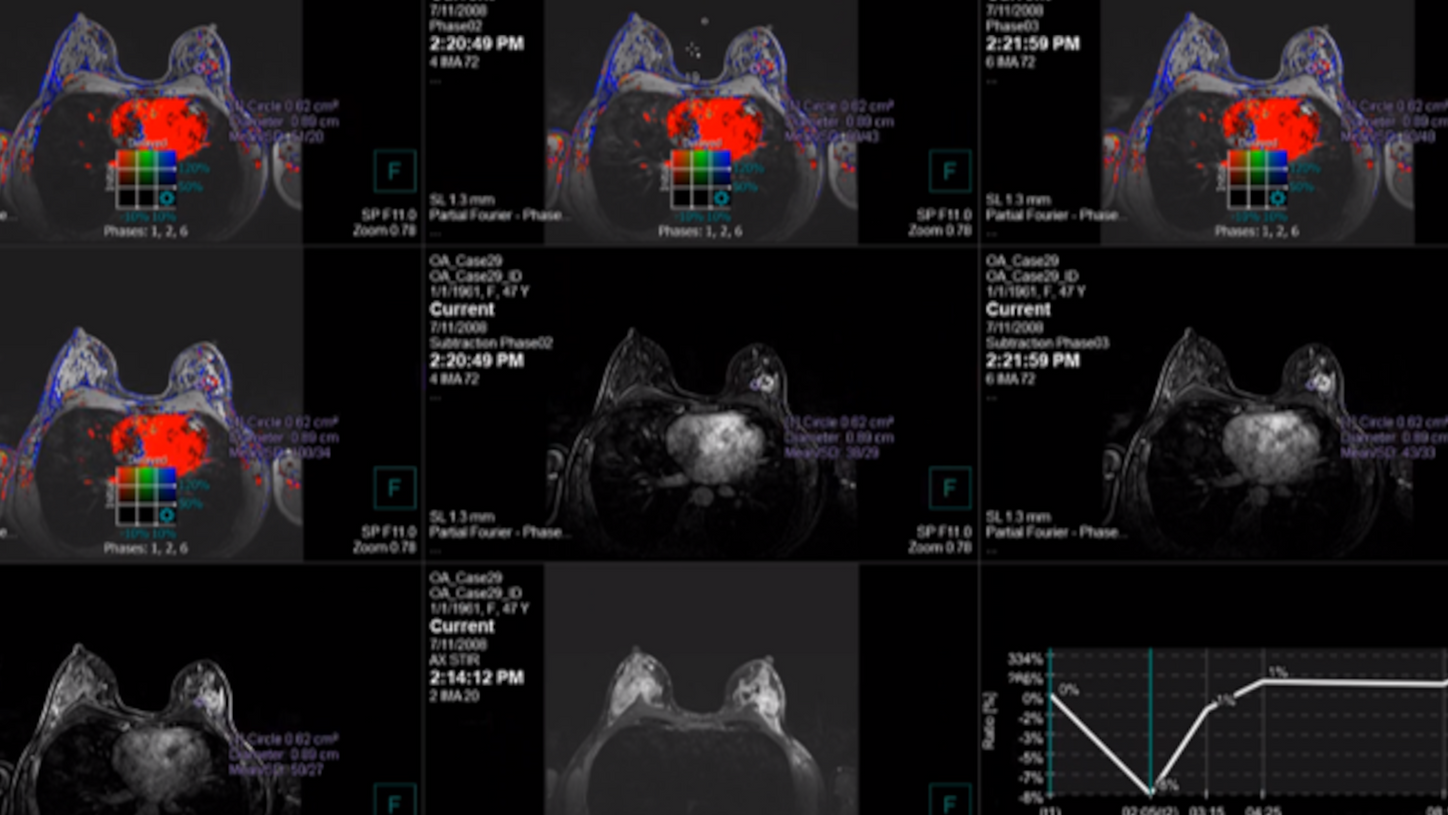

MAMMOVISTA B.smart deckt das gesamte Spektrum der Modalitäten ab – von der Mammographie über die MRT bis hin zum Ultraschall. Die agile, herstellerunabhängige Lösung bietet Radiolog*innen, die mit zeitaufwendigeren Tomosynthesebefundungen konfrontiert sind, eine hervorragende Performance.